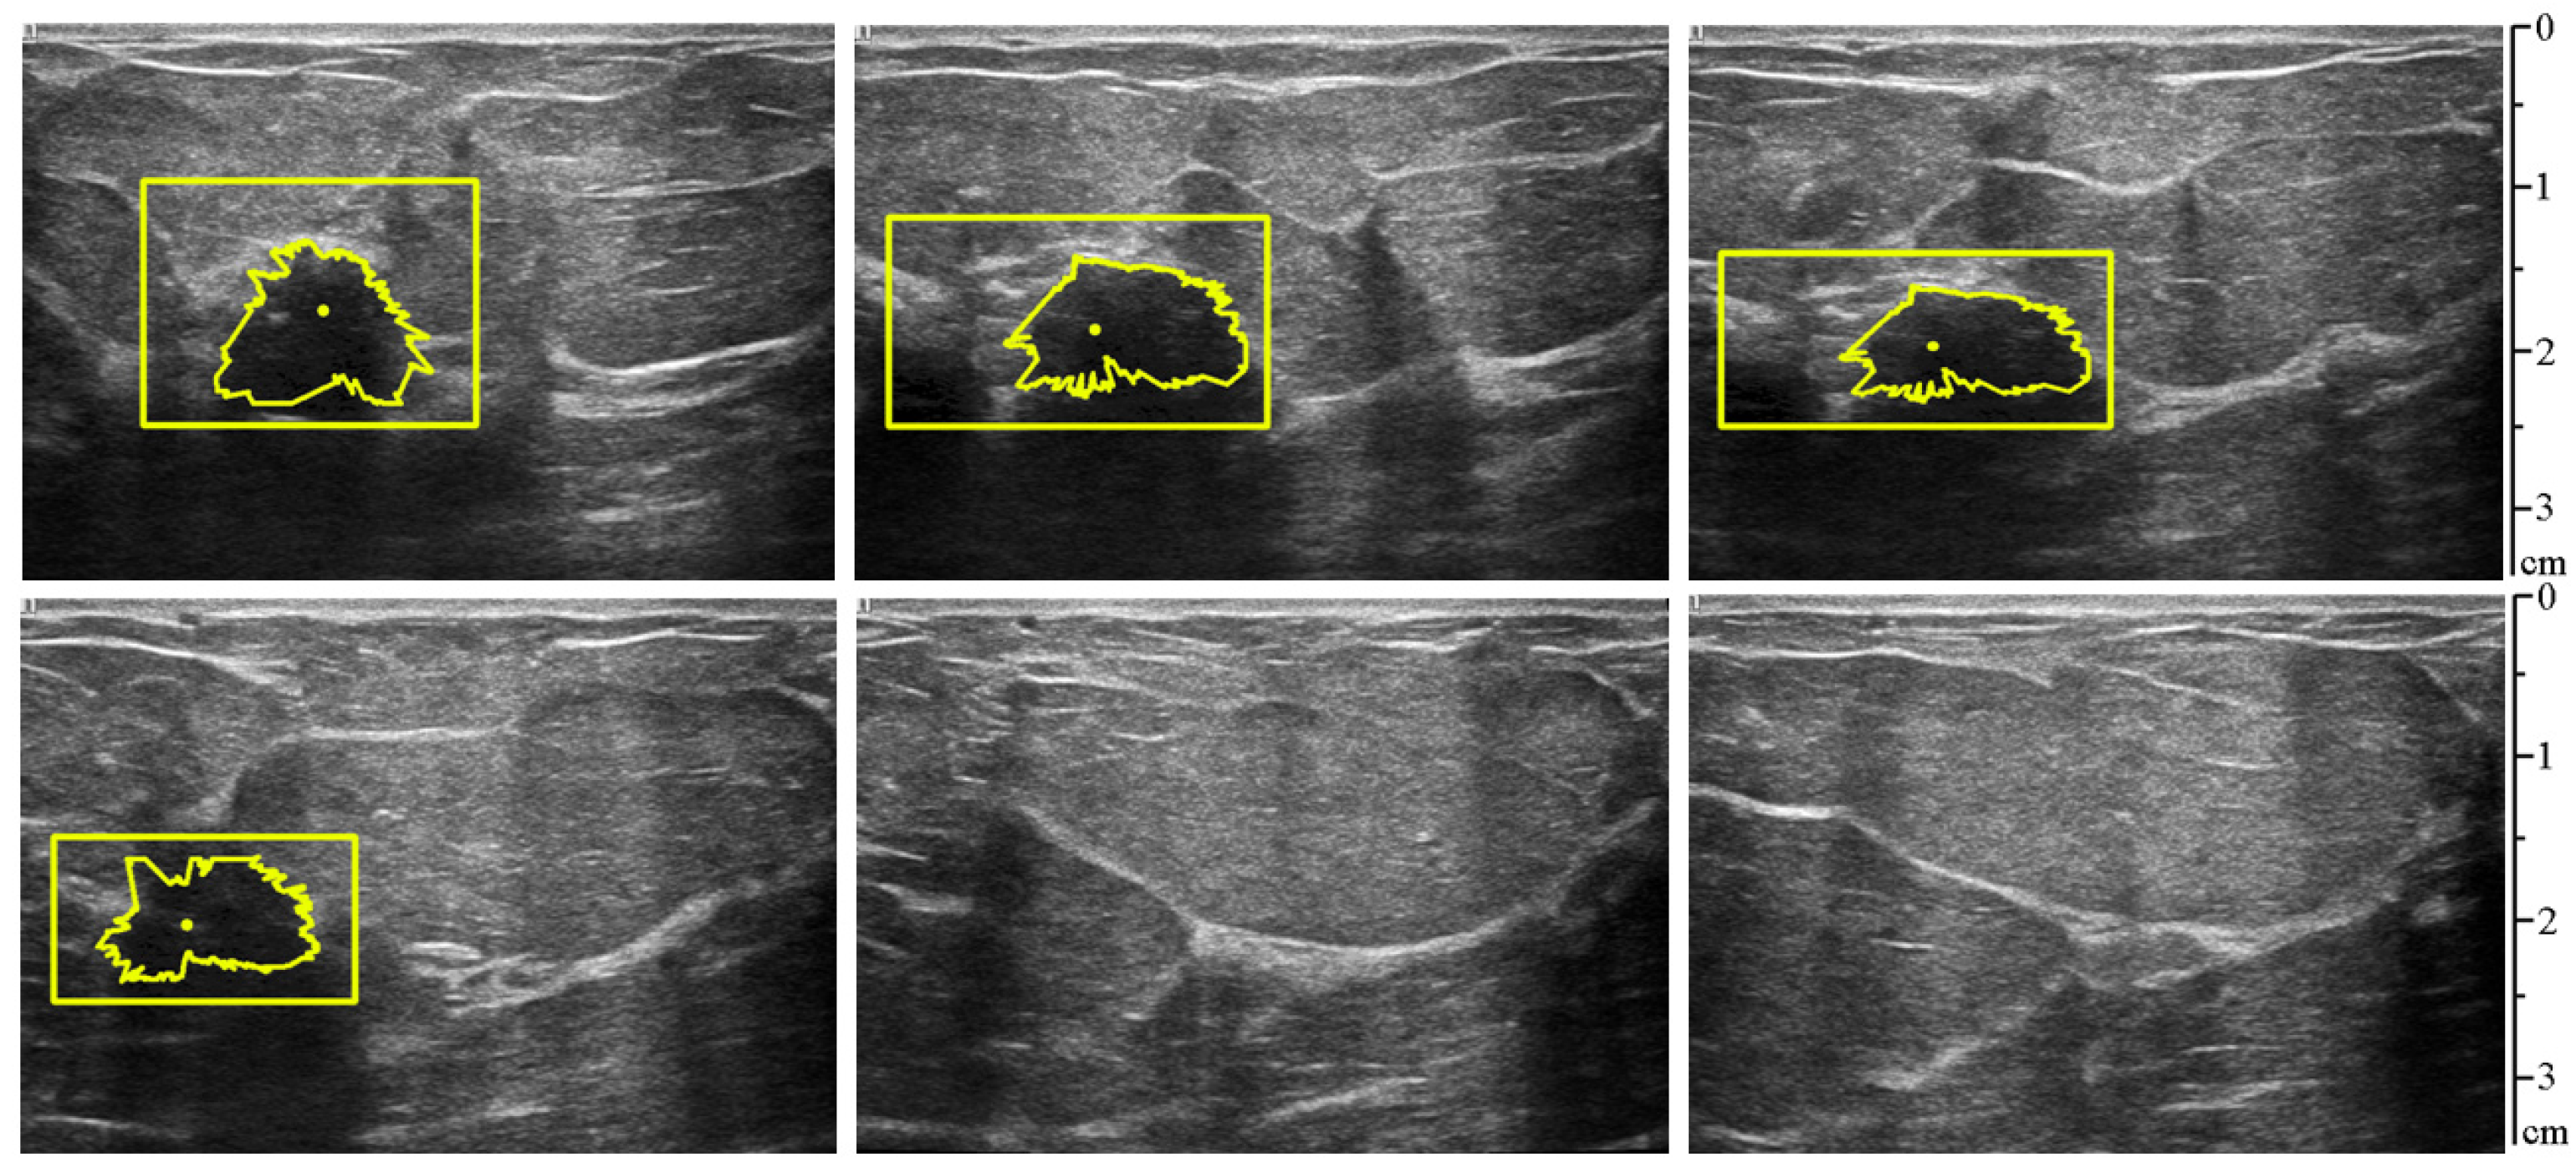

3.3. Testing of the Combined Method

3.2. Segmentation of Pathologic Lesion